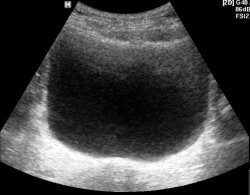

УЗИ мочевого пузыря - фотоОбычно, ультразвуковое исследование мочевого пузыря выполняется через переднюю брюшную стенку. У мужчин дополнительную информацию можно получить при исследовании через прямую кишку (ТРУЗИ), а у женщин при использовании вагинального датчика.